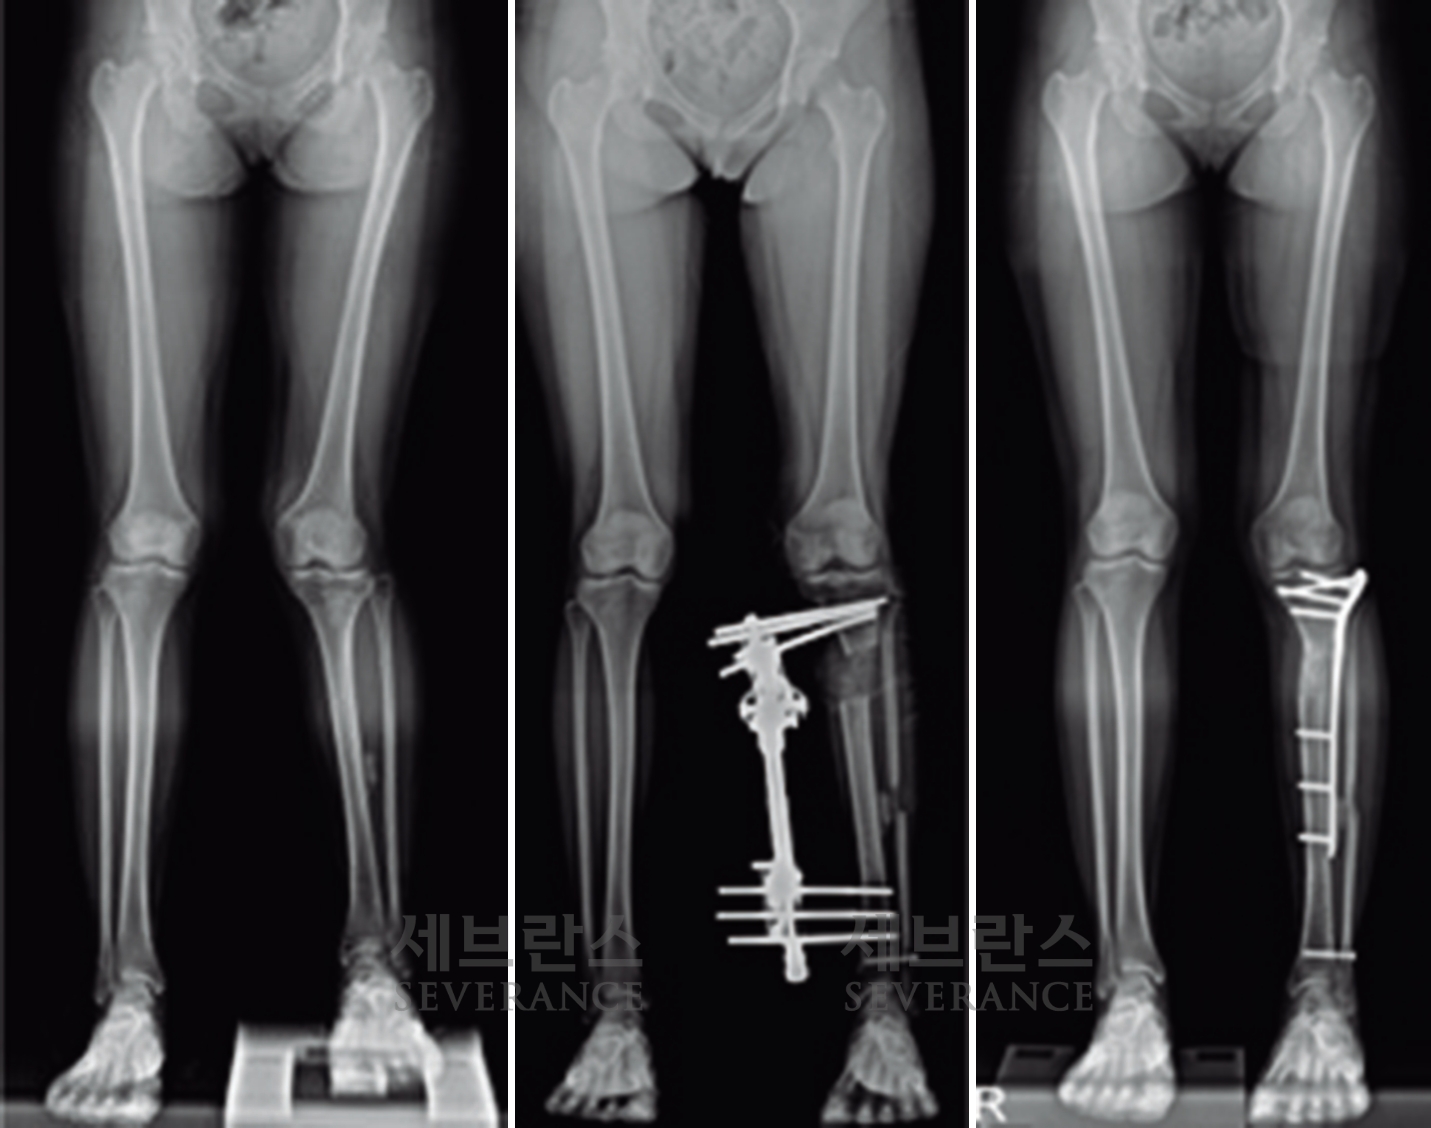

양쪽 팔다리의 길이 차이가 큰 경우에 주로 시행하는 수술로, 외부 고정 장치나 내부 금속정을 이용해 뼈를 서서히 늘려 균형을 맞추는 방법입니다. 대체로 외부 고정 장치를 많이 사용하는데, 연장 기간 동안 날마다 정해진 횟수만큼 뼈를 조금씩 늘려야 하고, 핀 주변 소독도 꾸준히 해줘야 합니다. 연장된 뼈가 단단히 붙는 데도 수개월이 걸리기 때문에 환자와 보호자의 인내가 필요합니다.

성장판 손상으로 발생한 좌측 외반슬 및 하지부동에 대해 골연장술과 교정술을 동시에 시행해 치료한 환아